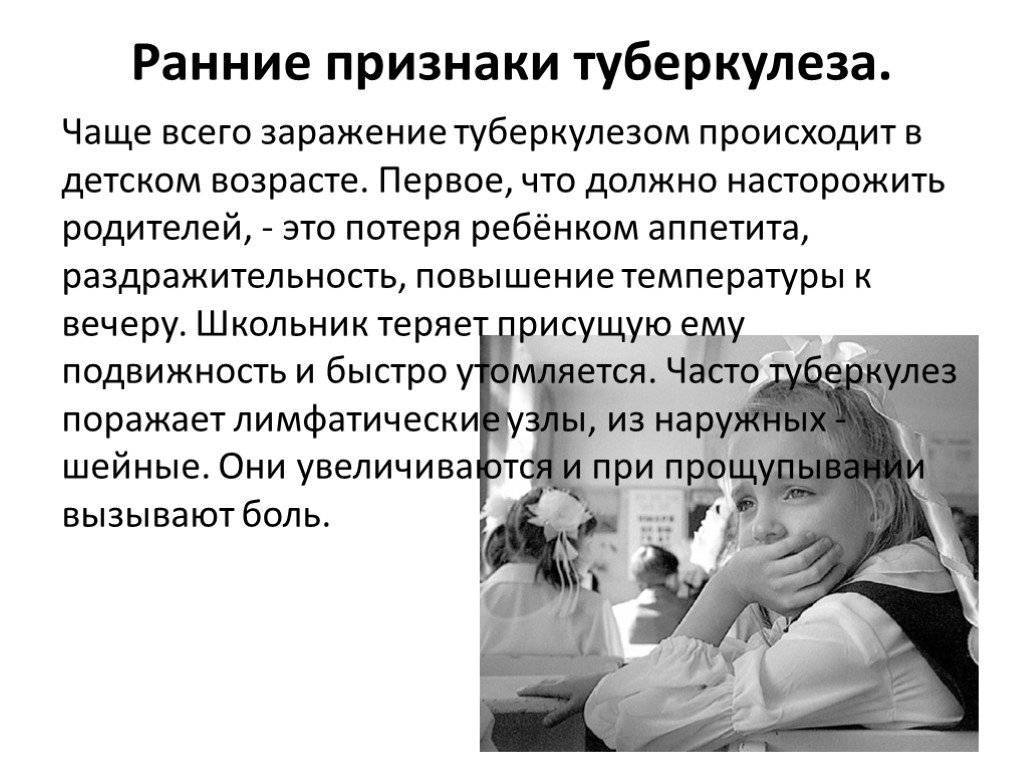

Симптомы туберкулеза: Как распознать и что делать

Раздел: Визуальные уроки